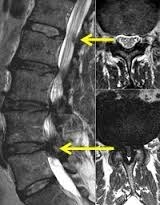

De diagnose wordt vermoed op basis van het klachtenpatroon. Het neurologisch onderzoek laat soms tekenen zien van een zenuwwortel-beknelling (pijn tijdens het oprekken van de zenuw of afwijkende reflexen aan de benen), maar kan ook volledig normaal zijn. Een MRI scan van de onderrug kan aantonen of er daadwerkelijk sprake is van een abnormale vernauwing van het wervelkanaal.